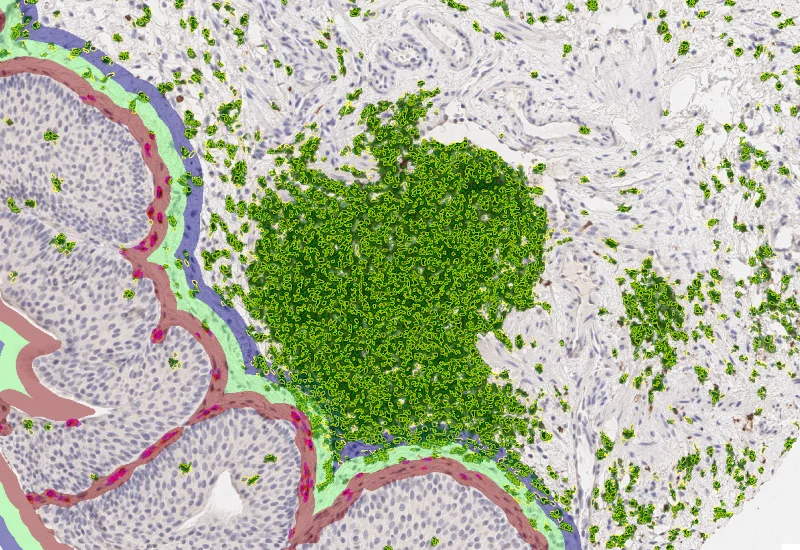

Nuclei detection

- Nuclei detection: Select input image, adjust nuclei size, configure background threshold, and remove nuclei by area or intensity.

- Cellular mask (immune marker channel): Generate cytoplasmic masks on the DAB channel; define automatic/manual background threshold, threshold range, max growing steps, and interior/exterior growth radius.

- Total cells: Number of detected nuclei per ROI/sample.

- Immune phenotypes: Number and percentage of DAB-positive immune cells (e.g., CD45+, CD3+, CD20+) in whole tissue and within each morphological entity.